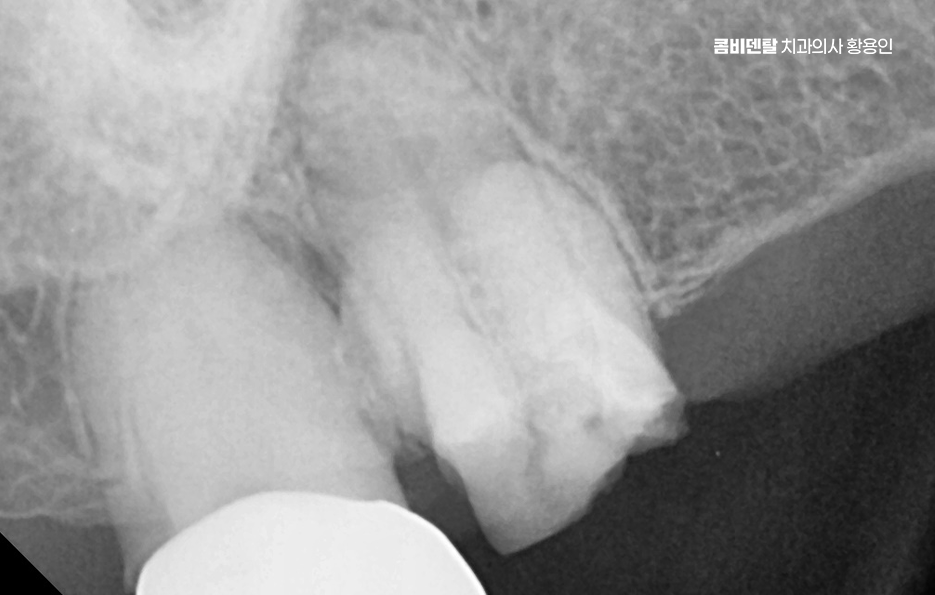

어금니가 빠지고 나서 어금니 임플란트 안하면 그 자리에 있던 치아가 받던 씹는 힘이 인접한 치아로 분산되기 때문에 그 치아들이 점점 기울거나 밀려나게 되고 결국 반대편 치아와의 맞물림도 흐트러지면서 전체 교합이 틀어지게 될 수 있어요

그뿐 아니라 맞물리는 반대편 치아는 치아가 빠진 공간 쪽으로 점점 윗니가 내려오거나 아랫니가 올라오게 되는데 이걸 정출 현상이라고 하며 결국 정출된 치아는 뿌리가 노출되고 시리고, 나중엔 치아 수명이 급격히 저하될 수 있기 때문에 어금니 하나 빠졌을 뿐인데 라고 생각하기에는 이러한 다양한 문제로 이어질 수 있는 거예요

이러한 문제를 막기 위한 효과적인 방법이 바로 임플란트 치료로 어금니 임플란트를 계획할 때는 먼저 잇몸뼈 상태를 정밀하게 확인해야 하며 3D CT 촬영을 통해 뼈의 높이와 두께, 그리고 임플란트를 심을 수 있는 공간을 세밀하게 분석해야 하며 위턱 어금니 같은 경우 상악동이라는 빈 공간이 바로 위에 있어서, 치아가 빠지고 나면 그 공간이 아래로 내려와 임플란트를 심을 자리가 부족해지는 경우가 많고 아래턱 어금니는 하치조신경이라는 중요한 신경이 지나가기 때문에, 신경을 피해서 정확한 위치와 각도로 식립하는 계획이 필요할 수 있어요